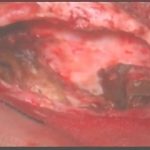

術中写真

摘出 前